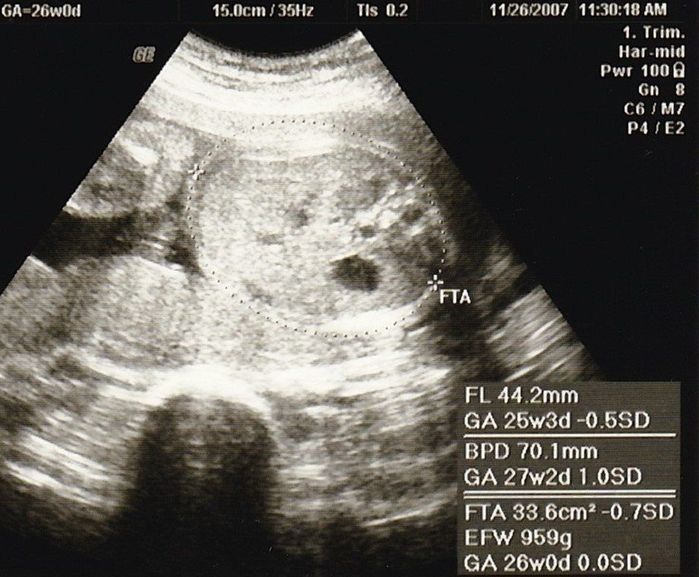

妊娠26週目のエコー写真

推定体重が1kg近くになりましたが、私の体重の増え方はそれを上回り、すでに約4kg増。おなかが重くなったせいか、睡眠が浅く、夜中に起きたり夢を見ることも多くなりました。私が子どものときに亡くなった祖父が、夢でお告げのようなものを語りかけてきたり、泣きながら目が覚めたりということもありました。